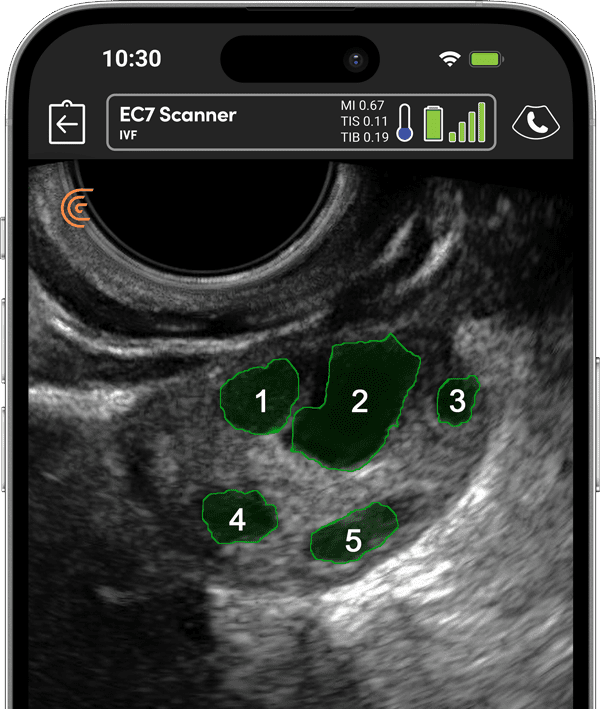

体外受精ツール

自動および手動の卵胞計数で不妊治療を最適化。